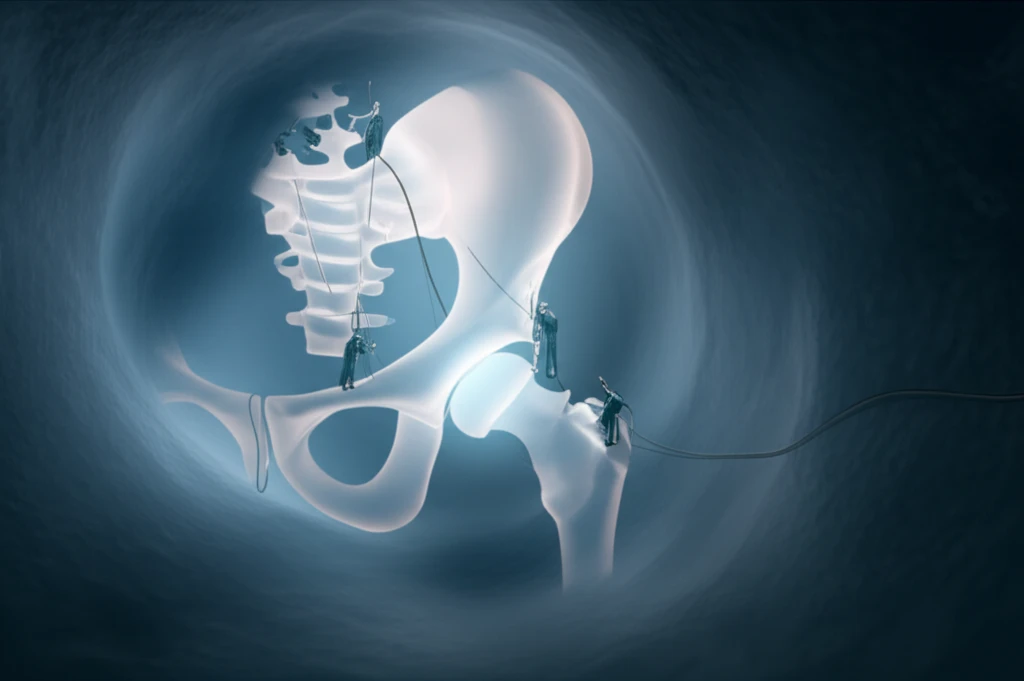

Traditional treatments have included repeated joint aspirations, open arthrotomy (surgical opening of the joint), and arthroscopic drainage. However, recent studies suggest that arthroscopic techniques, which involve smaller incisions and specialized instruments, can offer successful outcomes with potentially fewer complications.

This article explores a case where a 3-year-old child was successfully treated for septic arthritis of the hip using arthroscopic methods. This approach utilized a 2.7 mm arthroscope—typically used for ankle procedures—demonstrating a less invasive option for pediatric patients. This case highlights the potential benefits of arthroscopic surgery in even the smallest patients, offering hope for improved recovery and long-term joint health. With parental consent, data concerning her case would be submitted for publication.

- Specialized Instruments: Utilizing smaller arthroscopes and instruments designed for pediatric anatomy.

- Careful Traction: Employing techniques that provide adequate joint space without risking injury to the physis (growth plate).

- Precise Portal Placement: Choosing entry points that minimize the risk to surrounding nerves and vessels.